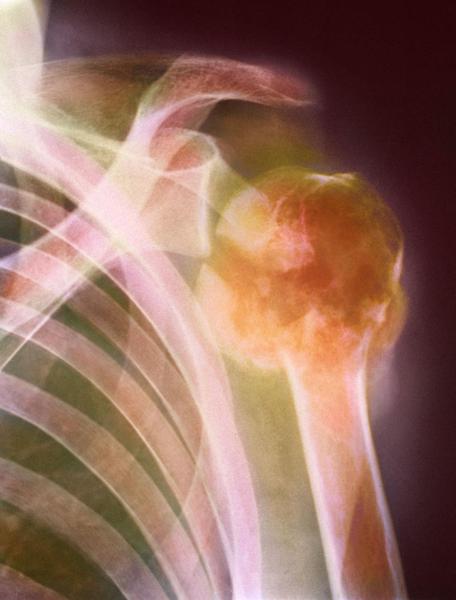

Multiple Myeloma Overview: Symptoms, Causes, Diagnosis, and Treatment

Multiple myeloma (also referred to as myeloma) is a type of rare, incurable cancer of the blood—also known as hematologic cancer. It affects cells called plasma cells, which are types of white blood cells. Normal plasma cells function to make antibodies, helping the body to fight infection. Myeloma involves malignant plasma cells that build up in the bone marrow or the soft tissue in the center of bones.

The term malignant describes the tendency to progressively worsen, invade, and destroy near